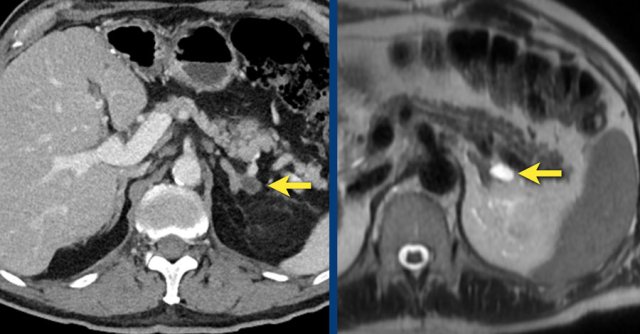

Here a small cyst is seen on CT and on a T2W-image.

Images show unenhanced and contrast-enhanced CT of a cyst.

The cyst is thin-walled, homogeneous and does not show any enhancement.